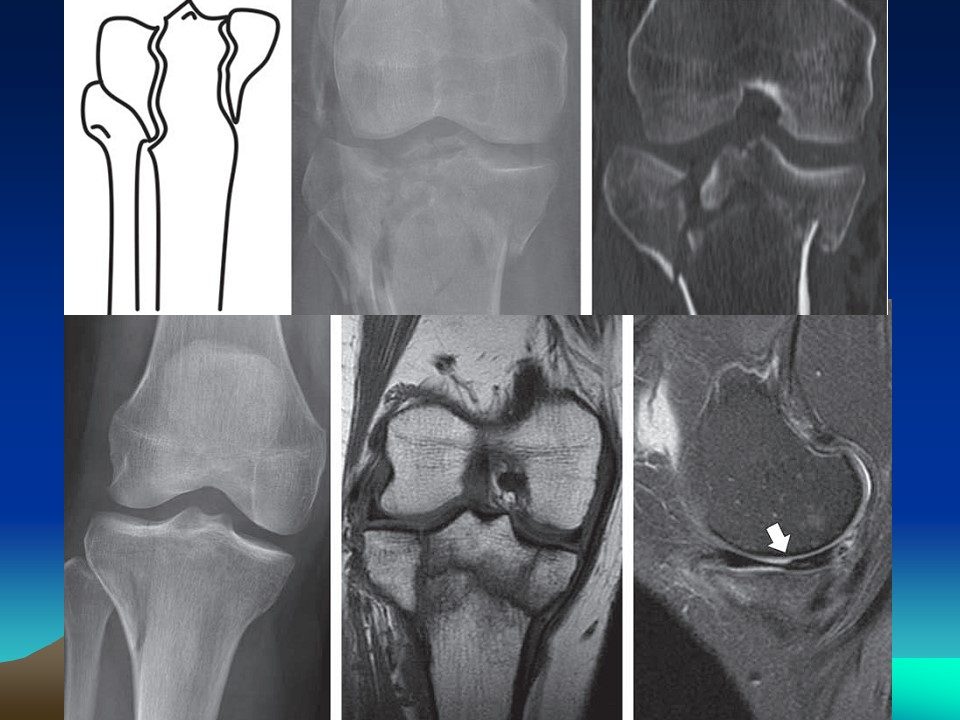

胫骨平台骨折的诊断及治疗PPT

胫骨近端骨折的一种

累及关节面

影响膝关节的力线、稳定、活动

占所有骨折1%,老年骨折8%

外侧平台受累为55%~70%,单纯内侧平台损伤占10%~23%,双髁受累有10%~30%。

治疗关键是保持肢体力线和关节面平整。应早期被动活动预防粘连。